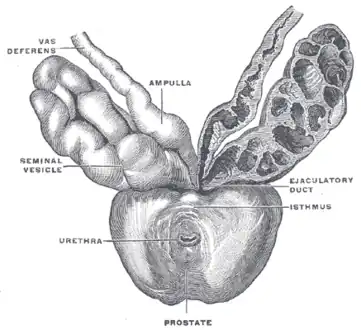

The seminal vesicles seen near the prostate, viewed from in front and above. | |

Structure

The human seminal vesicles are a pair of glands in males that are positioned below the urinary bladder and at the end of the vasa deferentia, where they enter the prostate. Each vesicle is a coiled and folded tube, with occasional outpouchings termed diverticula in its wall.[2] The lower part of the tube ends as a straight tube called the excretory duct, which joins with the vas deferens of that side of the body to form an ejaculatory duct. The ejaculatory ducts pass through the prostate gland before opening separately into the verumontanum of the prostatic urethra.[2] The vesicles are between 5–10 cm in size, 3–5 cm in diameter, and have a volume of around 13 mL.[3]

The vesicles lie behind the bladder at the end of the vasa deferentia. They lie in the space between the bladder and the rectum; the bladder and prostate lie in front, the tip of the ureter as it enters the bladder above, and Denonvilliers' fascia and the rectum behind.[3]

Seminal vesicles seen in a cadaveric specimen from on top, with the bladder to the bottom of the image, and the rectum at the top. Their position near the vas deferentia can be seen.

Seminal vesicles seen in a cadaveric specimen from on top, with the bladder to the bottom of the image, and the rectum at the top. Their position near the vas deferentia can be seen. -